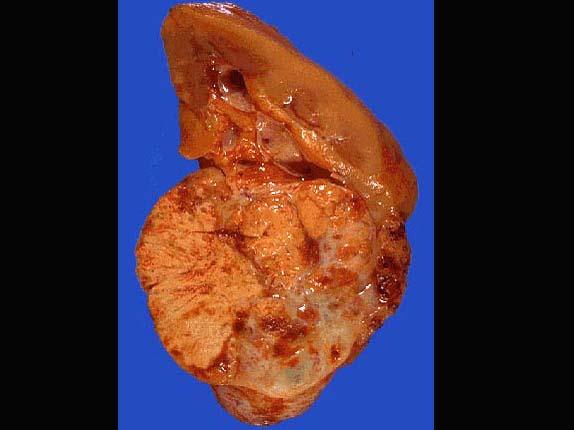

问题 男性,60岁,腰部疼痛不适3个月。B超示左肾下极肿物。明确诊断后行左肾切除术,患肾大体如图所示,镜下如图所示,关于该疾病说法错误的是 ( )

选项 A.发生部位以肾上下极多见 B.透明细胞癌为最常见的类型,占肾细胞癌的70%~80% C.起源于肾小管上皮细胞 D.烟草与该病的发生无关 E.可出现副肿瘤综合征

答案 D